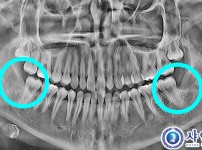

완전매복사랑니발치 - 구강외과전문의

해당 게시물은 의료법 제56조에 의거하여 로그인 후 열람이 가능합니다.